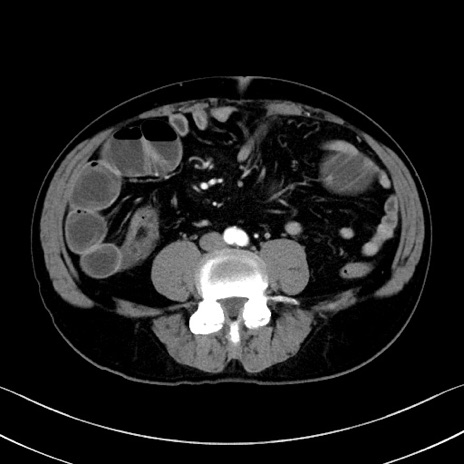

症例35(横断像)

【症例】70歳代 男性

【主訴】腹部膨満、嘔吐

【現病歴】昨日より腹部膨満感出現。本日増悪し、仙痛出現。嘔吐あり、受診。

【既往歴】糖尿病、胆摘後

【身体所見】BP 149/80mmHg、HR 74/min、BT 35.9℃、腹部:膨満、軟、圧痛なし。腸雑音減弱あり。上腹部正中切開瘢痕あり。

【データ】WBC 13500、CRP 1.72